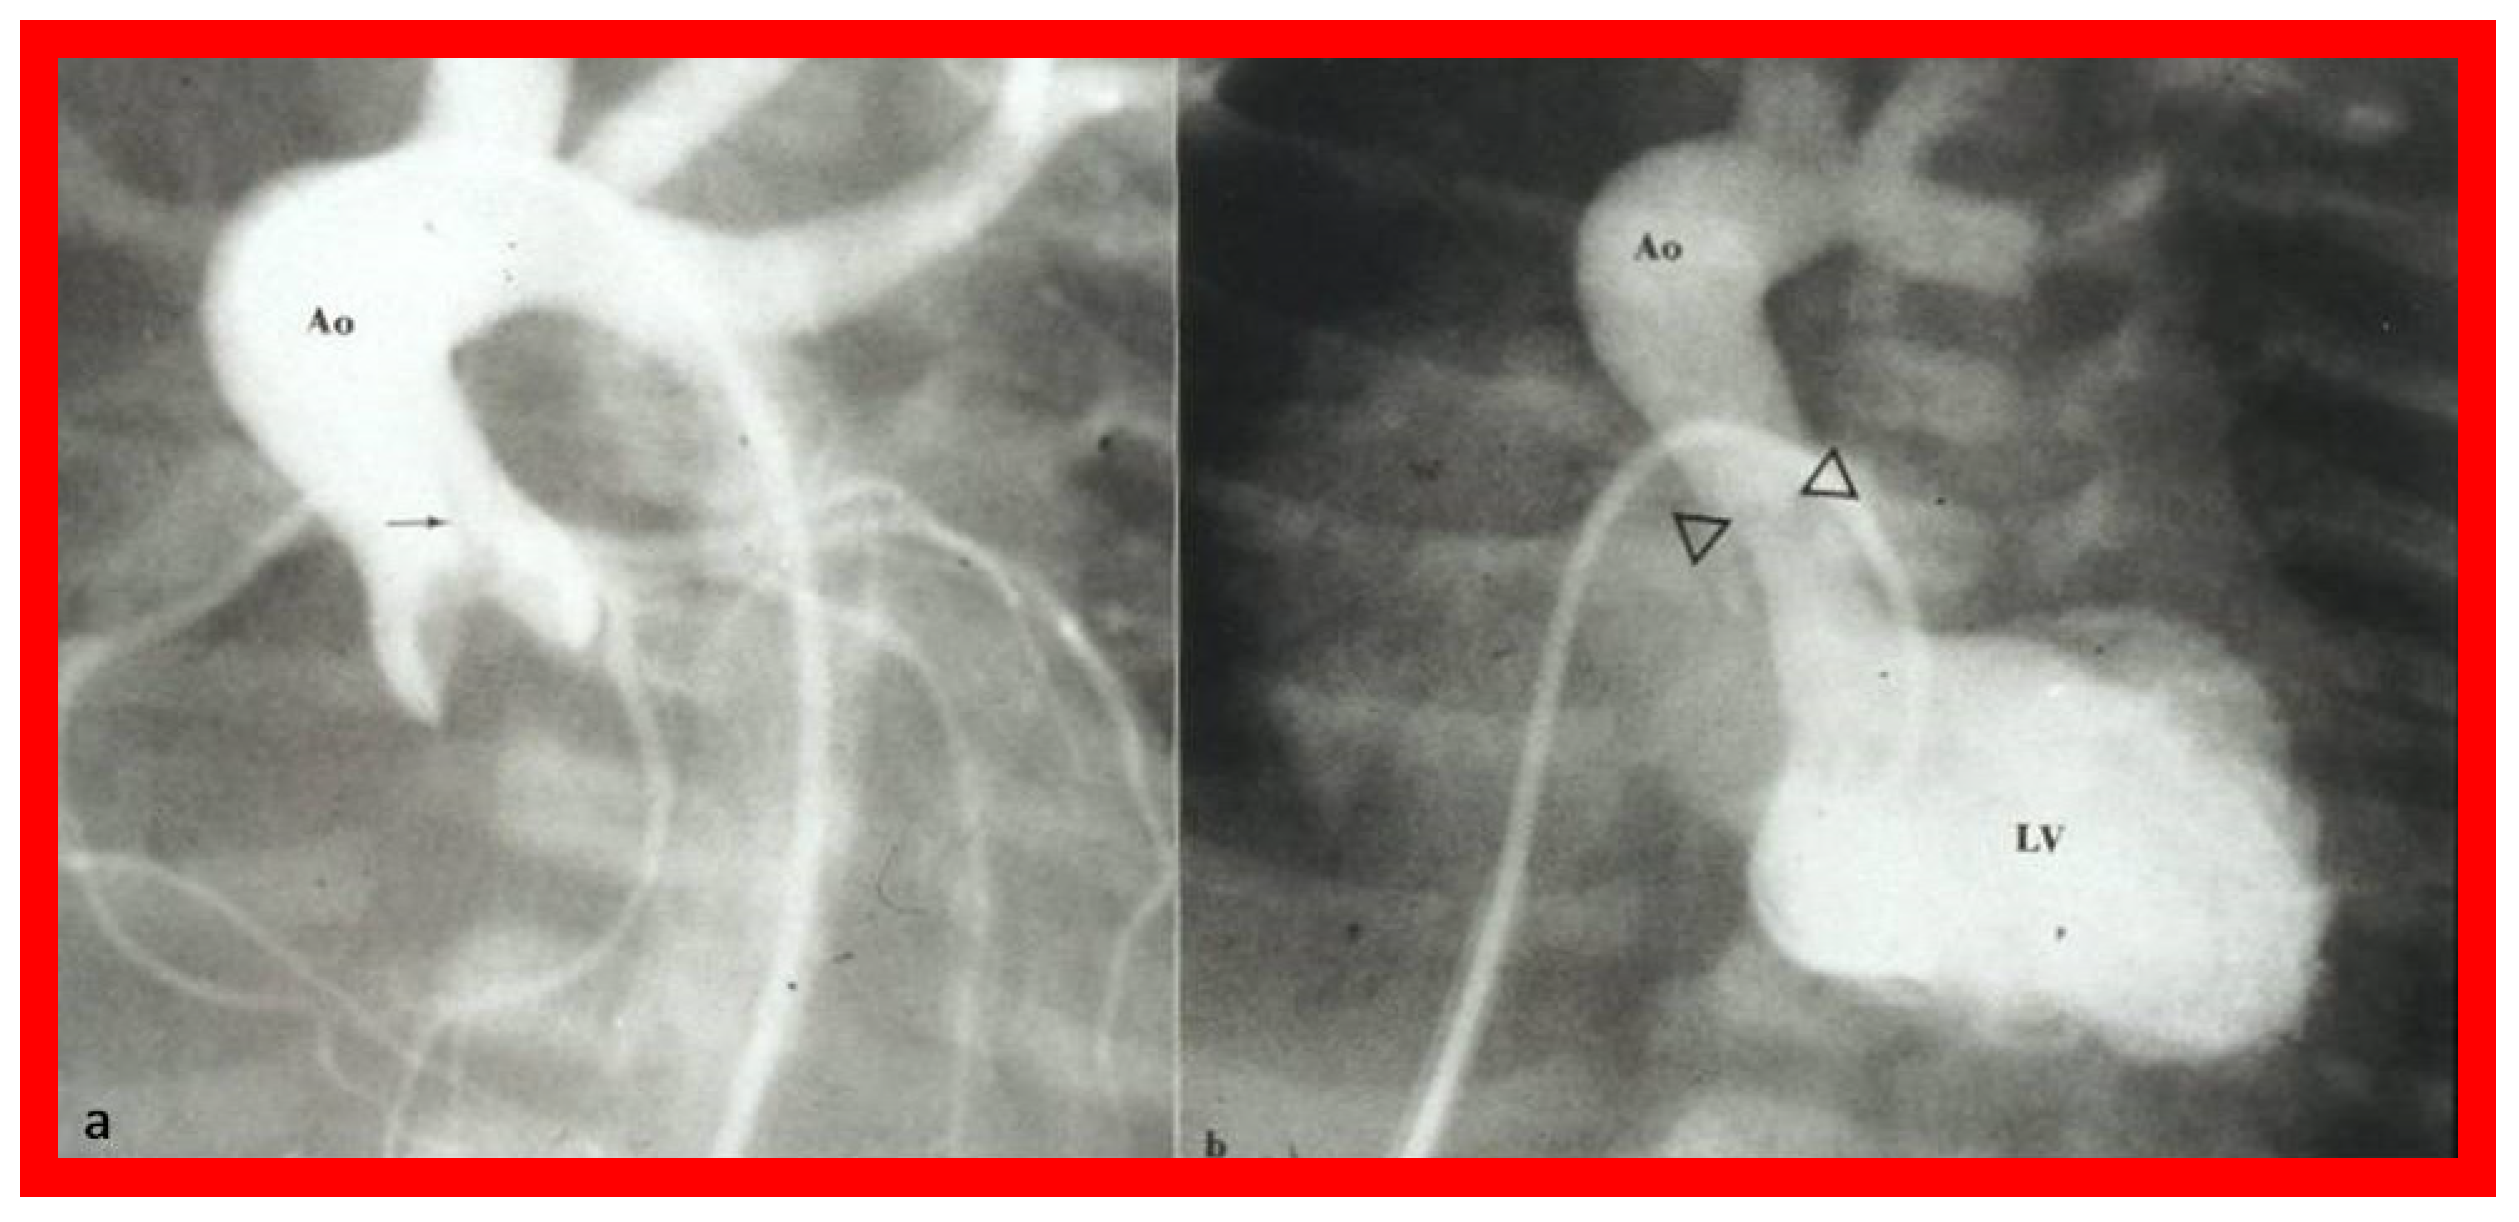

3.1. Causes of Aortic Insufficiency

- Galal, O.; Rao, P.; Al-Fadley, F.; Wilson, A.D. Follow-up results of balloon aortic valvuloplasty in children with special reference to causes of late aortic insufficiency. Am. Heart J. 1997, 133, 418–427. [Google Scholar] [CrossRef] [PubMed]

- Rao, P.S. Balloon aortic valvuloplasty. J. Interv. Cardiol. 1998, 11, 319–329. [Google Scholar] [CrossRef]

- Helgason, H.; Keane, J.F.; Fellows, K.E.; Kulik, T.J.; Lock, J.E. Balloon dilation of the aortic valve: Studies in normal lambs and in children with aortic stenosis. J. Am. Coll. Cardiol. 1987, 9, 816–822. [Google Scholar] [CrossRef] [PubMed]

- Phillips, R.R.; Gerlis, L.M.; Wilson, N.; Walker, D.R. Aortic valve damage caused by operative balloon dilatation of critical aortic valve stenosis. Br. Heart J. 1987, 57, 168–170. [Google Scholar] [CrossRef] [PubMed]

- Sholler, G.F.; Keane, J.F.; Perry, S.B.; Sanders, S.P.; Lock, J.E. Balloon dilatation of congenital aortic valve stenosis: Results and influence of technical and morphological features on outcome. Circulation 1988, 78, 351–360. [Google Scholar] [CrossRef] [PubMed]

- Shaddy, R.E.; Boucek, M.M.; Sturtevant, J.E.; Ruttenberg, H.D.; Orsmond, G.S. Gradient reduction, aortic valve regurgitation and prolapse after balloon aortic valvuloplasty in 32 consecutive patients with congenital aortic stenosis. J. Am. Coll. Cardiol. 1990, 16, 451–456. [Google Scholar] [CrossRef]

- Rocchini, A.P.; Beekman, R.H.; Ben Shachar, G.; Benson, L.; Schwartz, D.; Kan, J.S. Balloon aortic valvuloplasty: Results of the Valvuloplasty and Angioplasty of Congenital Anomalies Registry. Am. J. Cardiol. 1990, 65, 784–789. [Google Scholar] [CrossRef]